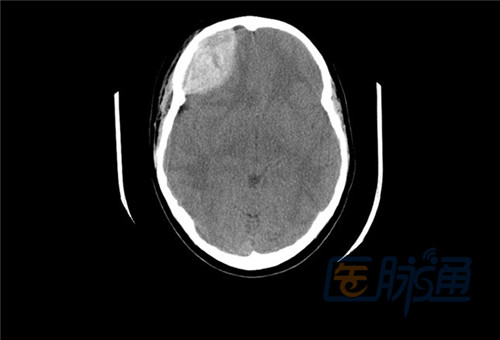

颅脑损伤一般可分为头皮软组织伤,颅骨损伤和颅内组织损伤。CT可直接显示血肿和脑挫裂伤。影像学表现:CT

第四节颅脑损伤头皮软组织伤颅骨影像学表现CT:、内板下局限梭形均匀密度影一般不超过颅缝、占位征象、骨折

影像学表现:CT 损伤区局部呈低密度改变。散在点片状出血 蛛网膜下隙出血 占位及萎缩表现 合并其他征象 影像

并归纳总结常见的头皮占位性病变的特点以及影像表现的共性,以期为临床头皮占位性病变提供有